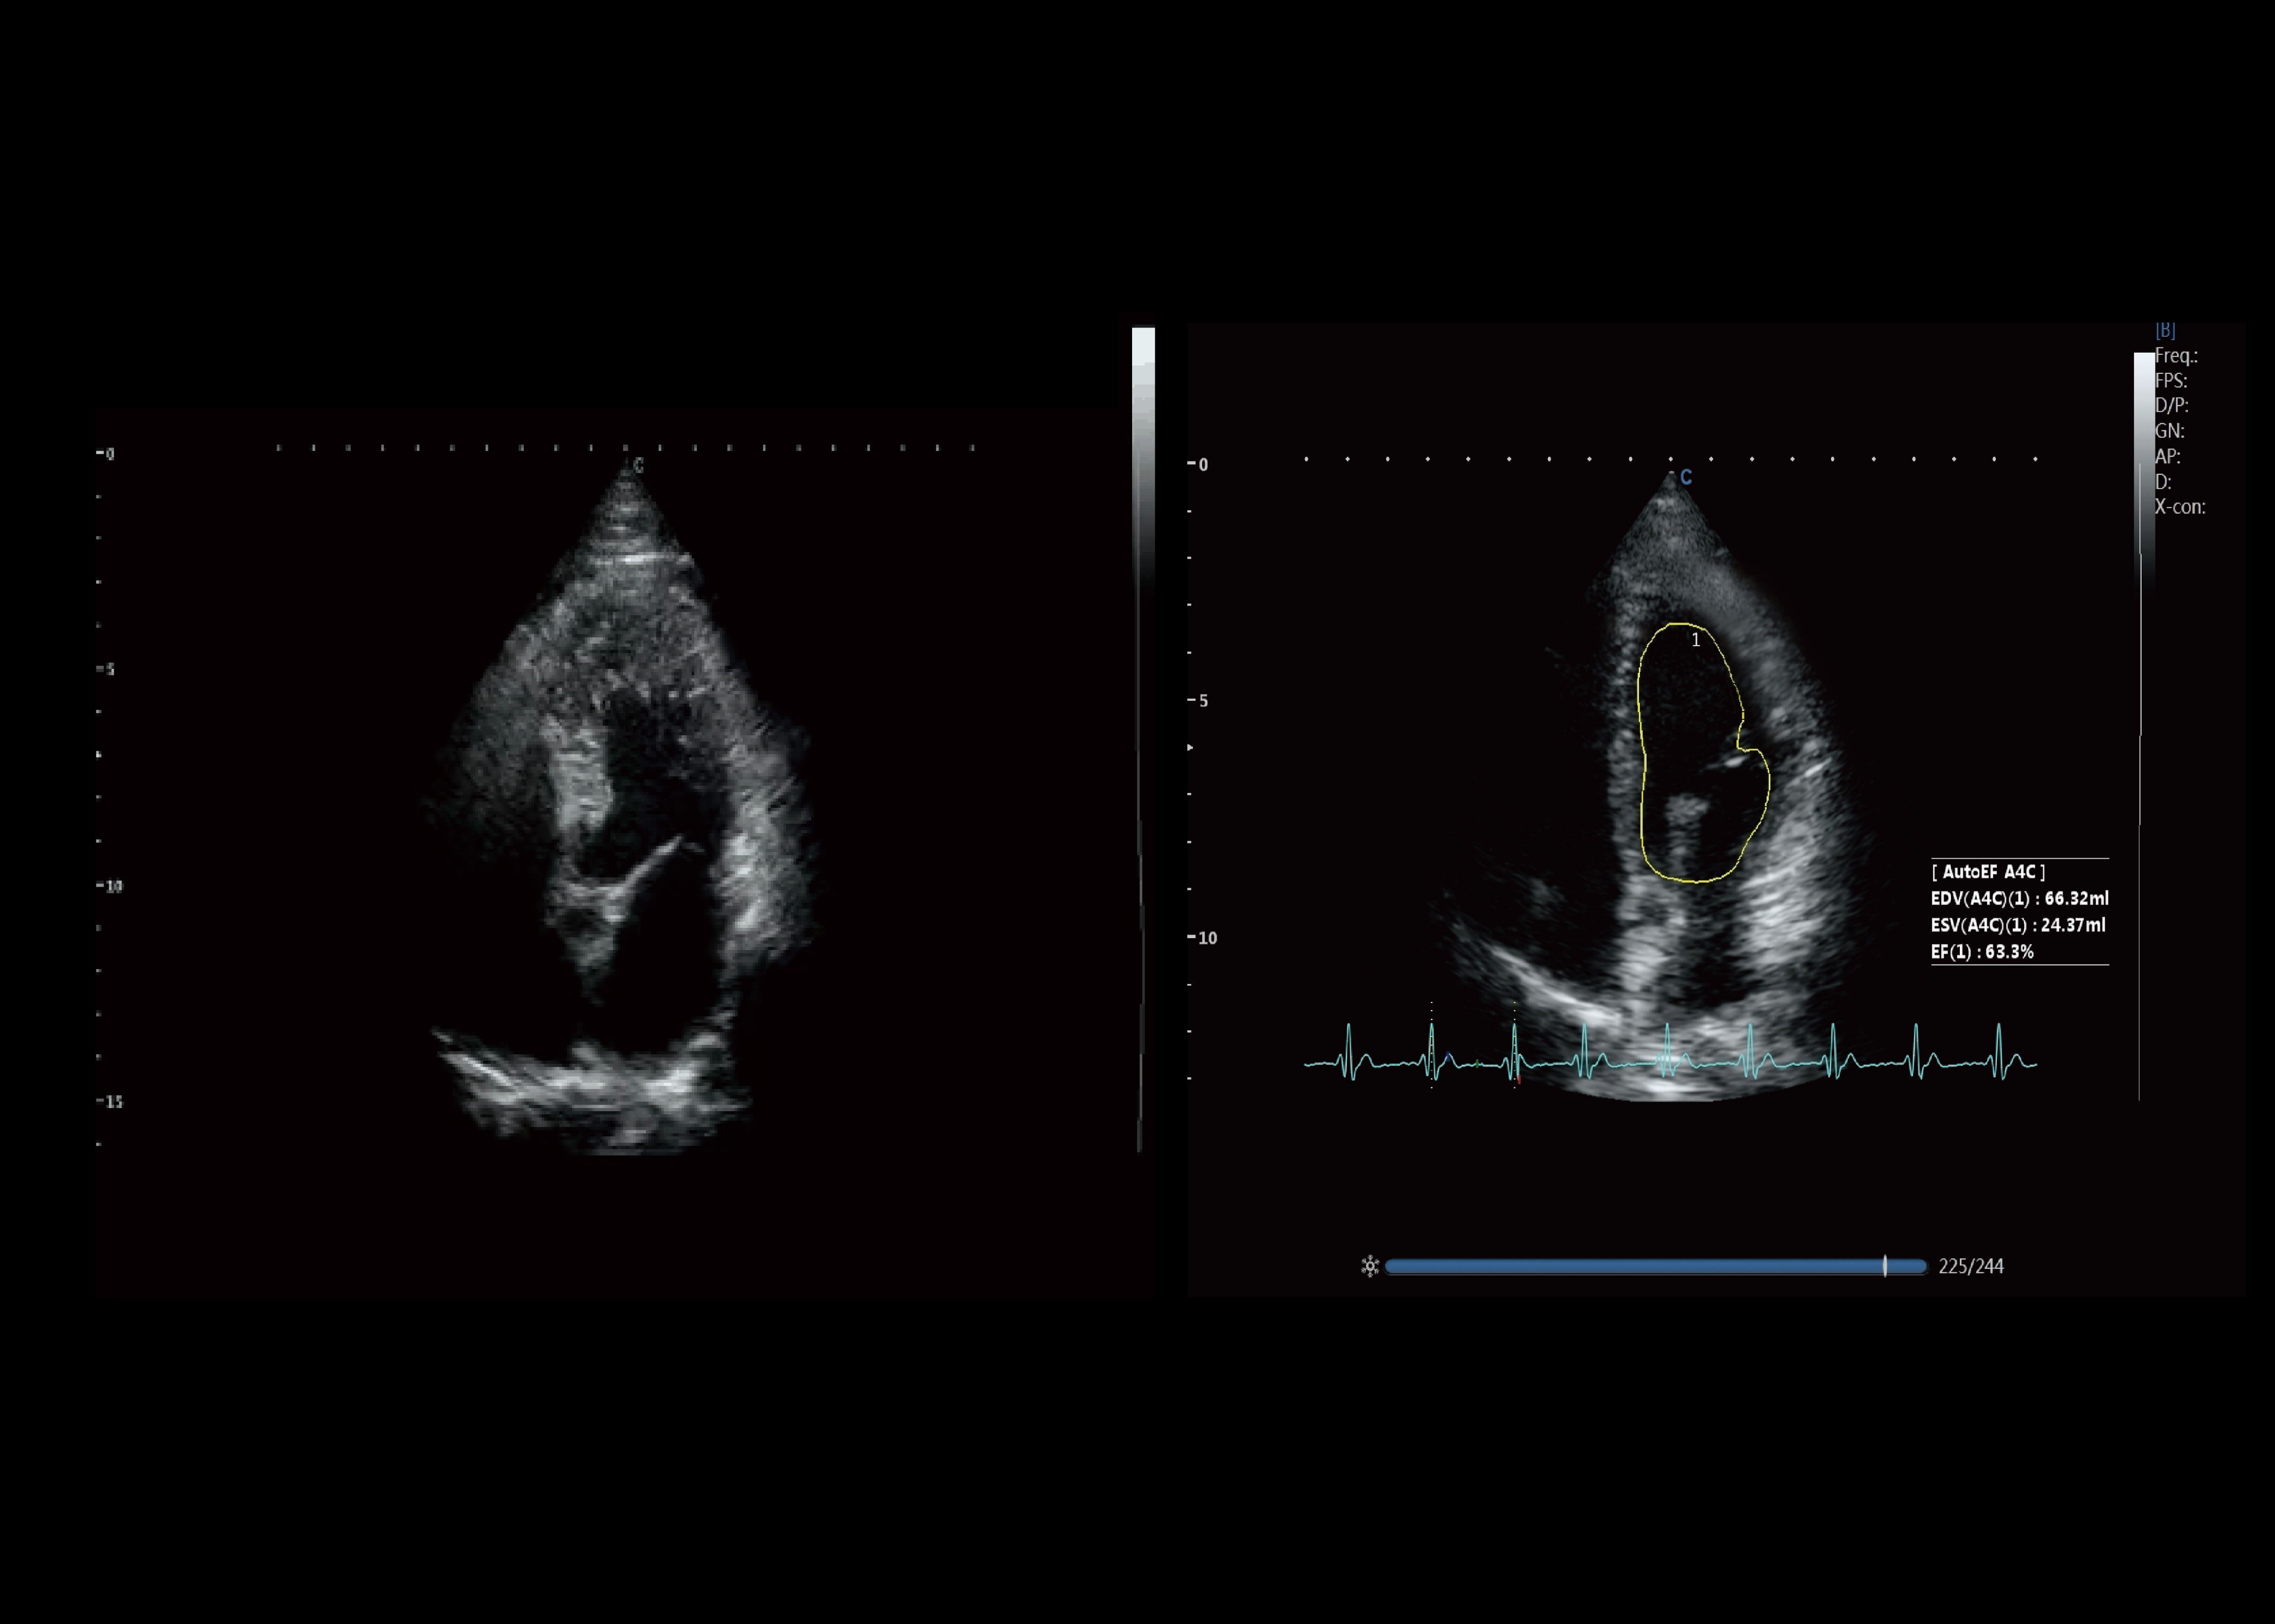

Austausch von Kardioloischen fällen / Update

Die Bedeutung der kardiologischen Untersuchung wird durch die ständig zunehmende Häufigkeit von Herzerkrankungen unterstützt. CHISON XBit 90 kann eine höhere Empfindlichkeit bieten, die für die Erkennung bestimmter Erkrankungen erforderlich ist, und hilft Ärzten, mehr Vertrauen bei der Durchführung von Herzuntersuchungen zu gewinnen.

Auto EF

● Automatisches Erkennen und Umhüllen des Endokards genau und liefern Messwerte der Herzfunktion (EDV,ESV,EF) synchronisiert.

● Deutliche Verbesserung der Arbeitseffizienz.